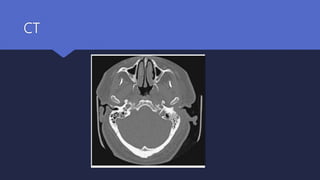

 Ct scan :

Defines the anatomical extent of the disease

Remains the initial investigation of choice

CT

Diagnosis Radiological investigations  Ctscan : Defines the anatomical extent of the disease Remains the initial investigation of choice  MRI scan Useful for assessing the initial severity of the disease Excellent at delineating the extent of soft tissue disease Intracranial complications

• #18 CT scan showing the soft tissue obliterating left external auditory canal left mastoid, infra-temporal fossa, skull base and involving the left TMJ.

• #19 Axial CT scan of a 63-year-old patient who has diabetes and left malignant otitis externa showing bony erosion of the posterior external auditory canal and mastoid cortex